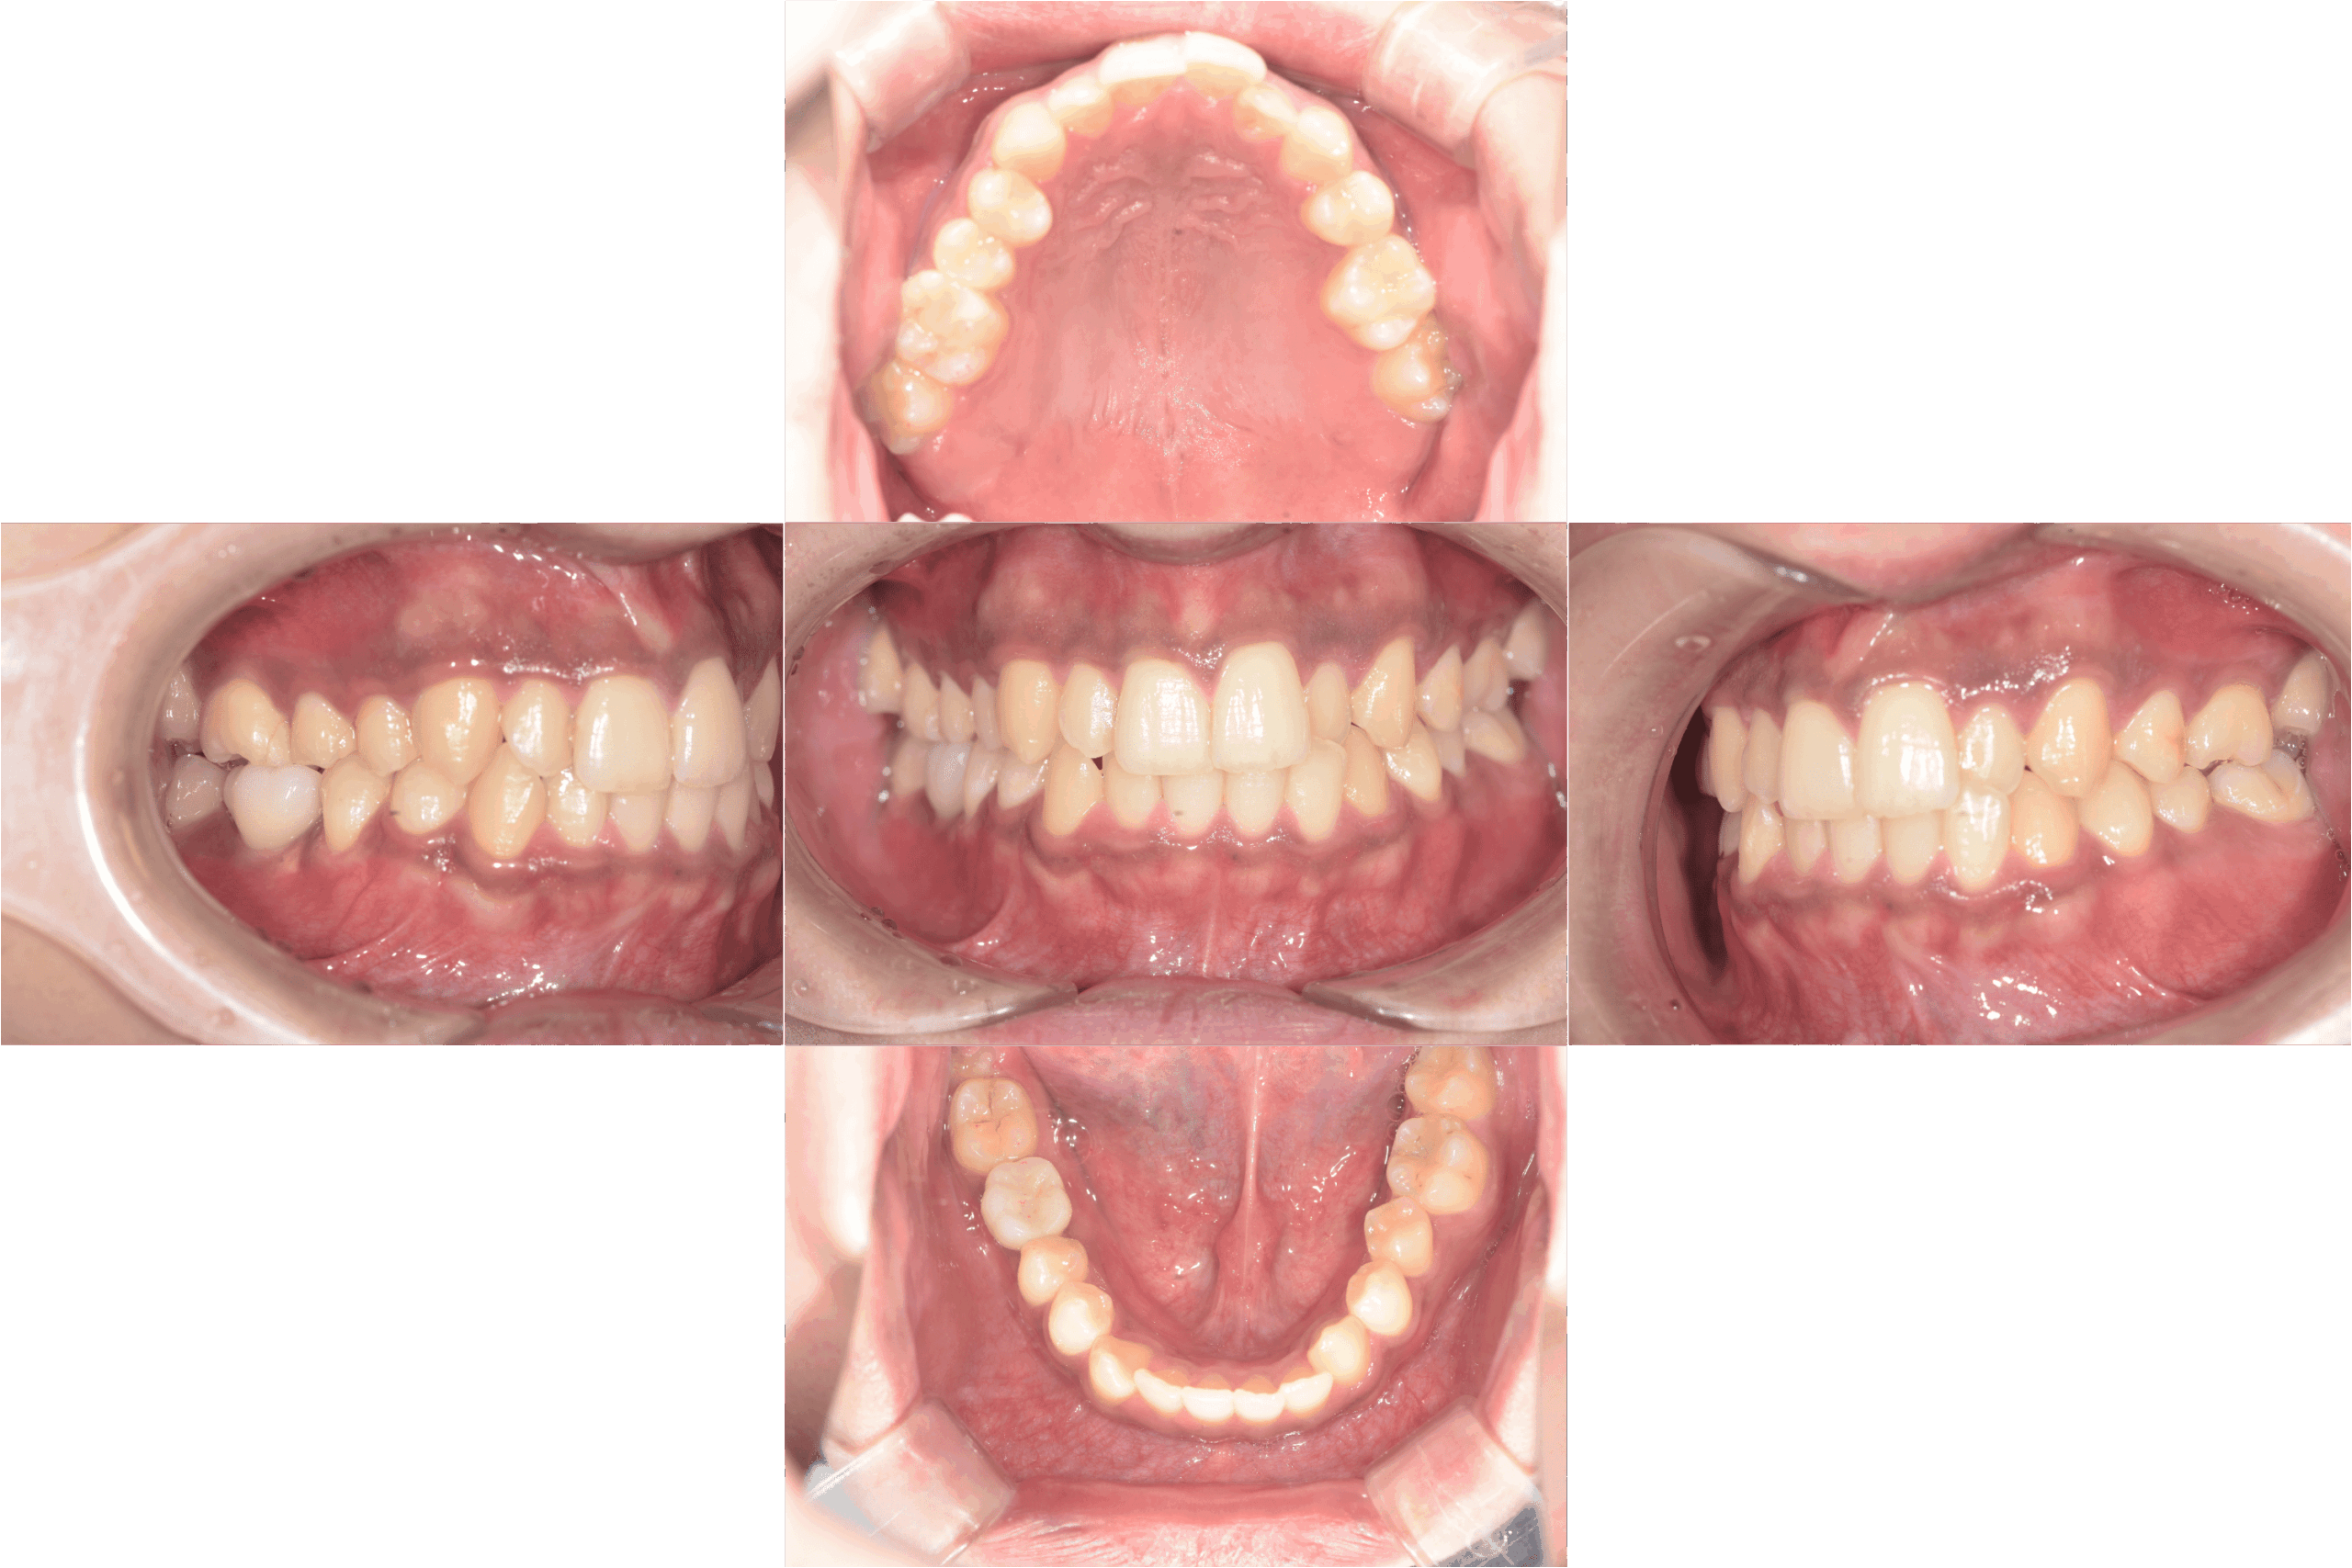

治療後口腔内写真